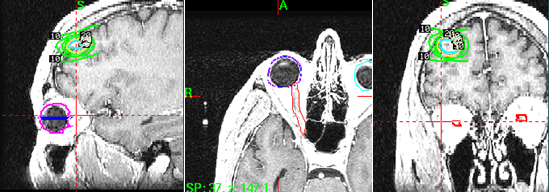

To guarantee the accuracy of our analysis, a series of procedures were followed to check the calculation. Our methodology was derived from analysis of a simple shape, a complicated structure, and a clinical case. And this approach guided us throughout the process of developing this algorithm. A cube was chosen to make certain that all voxels remained within the boundary of the polygon. We used the semi-circular cylinder because the circumference of a circle approximately represents an infinite number of sections of line. Then a clinical case was used to show the application of the Monte Carlo integral dose and the calculation benefit in the analytical Gamma Knife dose model. The Gamma Knife dose model can be calculated based on the measurement of the helmet and some of the reference points.8 The Gamma Knife C model dose simulation was verified by the profile comparison, which is shown in figure 2, where the 2-dimensional dose profiles can be seen along the x, ,y and z axes. The solid data point was directly extracted from the Leksell Gamma Knife Treatment Planning System (LGKTPS).

Figure 2 Simulation of Leksell Gamma Knife C model in x, y, z directions. The diamond points are the data from LGK TPS. The solid line is from the computed model.

Monte Carlo calculation of the integral dose in a clinical case involving eye lens shielding during Gamma Knife treatment

Eye lens dose is a concern in radiation treatment of ocular cancer.10,11 However, determining which beam should be plugged is difficult, especially when the eye lens is far away from the treatment target. Figure 10 illustrates such a circumstance. Combining the Monte Carlo integral dose model and the analytical dose model, we can easily generate a blocking pattern that will decrease the eye-lens dose by more than 50%. This result is shown in Table 1. In this case, we prescribed the dose to average center of the 9 shots. The critical structure was defined as the lens of the right eye, and reference point dose was prescribed to the center of this structure. The dose was decreased is up to 81.7% by selecting 3 beams to block. These data suggest that blocking beam selection is a mechanism that is sufficiently sensitive and effective for integral dose calculation. Therefore, the Monte Carlo integral dose calculation method can be an effective tool in selecting beams to block to protect organs at risk in Gamma Knife treatment plans.

Figure 10 Eye lens dose avoidance using Monte Carlo Integral dose calculation.